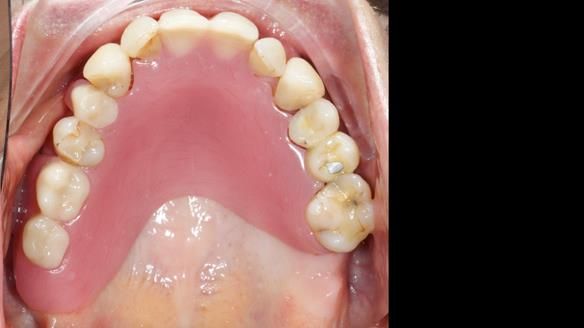

She had previously suffered from generalised periodontitis – stage IV, grade C, currently stable, with reduced attachment across the upper arch.

By the time she came to me, her periodontal condition was stable — but the aesthetics in the upper jaw were very poor.

We provided her with an immediate upper denture (Mk 1), followed by a definitive metal-based upper denture (Mk 2). A lower removable partial denture was discussed, to be made only if needed once the upper treatment was complete. However, at review, this wasn’t necessary — Adnana had excellent neuromuscular control and function, even with a shortened dental arch (SDA).

Rowan, Sam Hesketh and Chris Hesketh provided the stunning technical work. I am very lucky to have them.